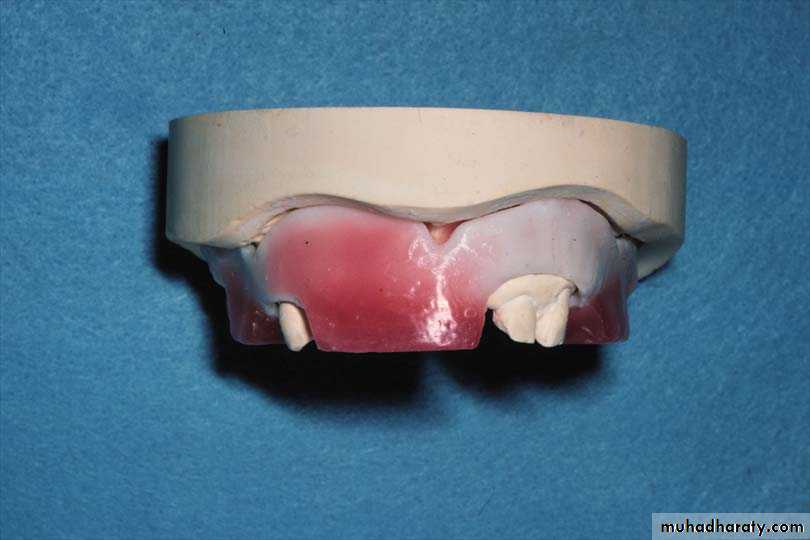

Replacement of the natural teeth by artificial teeth :When it is decided to place the anterior teeth in their original position, the following steps should be done :

Upper and lower impressions, with the dentures in position, are made and poured with dental stone.

One stone tooth by one is removed and replaced by artificial tooth in the same position; the position of each individual tooth can be more easily copied.

Root sockets are prepared in the stone models into which necks of the artificial teeth are fitted

The labial root portion of the teeth is excavated to approximately I mm on the labial side and flash with the gingival margin on the lingual or palatal side. The depth of the socket should never exceed 5 mm